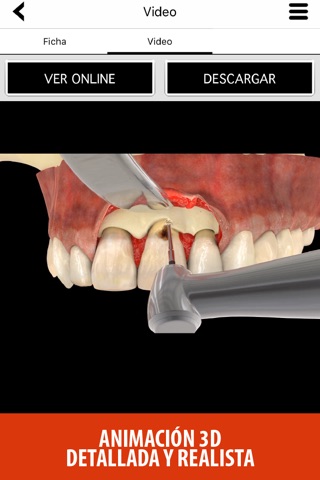

- Animación 3D detallada y realista.